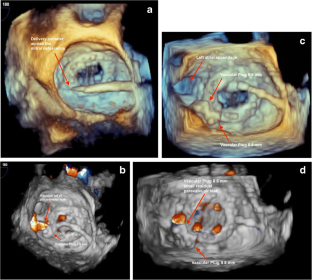

Fig. 3